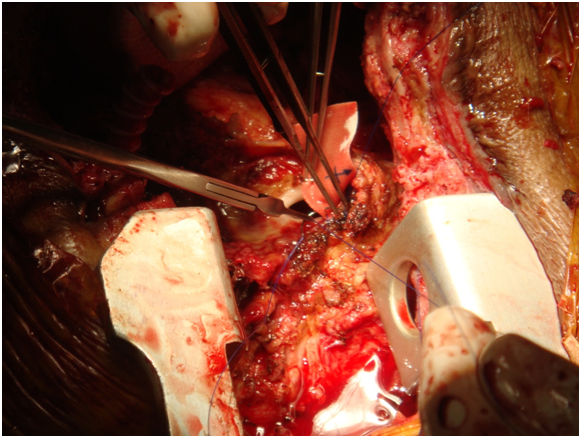

Chest incision was very technical-started from below with oscillator saw upto upper 1/3rd of sternum near aneurysm. Now upper part from above-near aneurysm curved the saw to right avoiding the aneurysm, put small retractor now gradually cut through bony surface so not went into graft and go around aneurysm without rupturing it but suddenly aneurysn came to leak--now no way--gentle pressure on leak and proceeded for total circulatory arrest. During going to total circulatory arrest, dissection around heart was done through diaphragmatic surface and right side. Now at 180C total circulatory arrest was done, taken out graft, found oval shaped opening at ascending aorta, a Dacron patch taken and covered it by continuous proline suture.

Started rewarming and circulation, Distal part of graft on axillary artery found-a silk ligature applied- rest of the graft taken out. Weaning from CPB was done easily, sternal wound reconstruction was done with pectoral is major muscle flap. The patient was discharge from the hospital on 7th post operative in good general condition. Now more than 2 years follow up he is doing very well [2] (Figures 1-10).

Figure 8: Oval shape opening at ascending aorta, a Dacron patch taken and covered it by continuous proline suture.

Figure 9: Oval shape opening at ascending aorta, a Dacron patch taken and covered it by continuous proline suture.